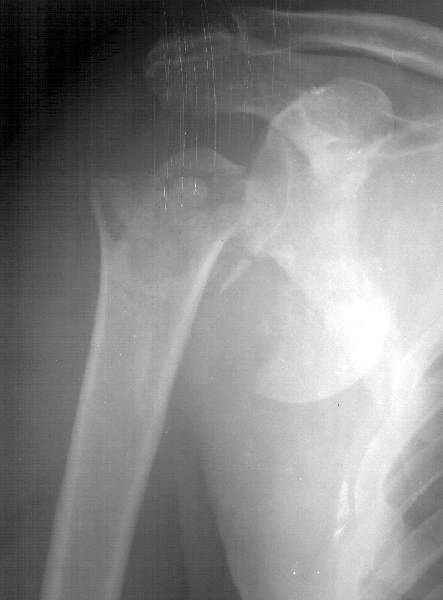

Мужчина 61 г., получил 6.04.02 в ДТП (лобовое столкновение) вывих плеча с переломом большого бугорка и не бросающимся в глаза переломоманатомической шейки (см здесь ). В ЦРБ под в/в наркозом дежурный врач (ЛОР по специальности) попытался вправить плечо. Контрольный снимок

сделан через день (фас, аксиальная). Из сопутствующей патологии - болезнь Рейно, 2 года назад какая-то сосудистая операция (выписки нет, 15 см рубец под мышкой), от которой положительного эффекта не отметил.Есть холодность и мраморность предплечья и кисти, стойкие контрактуры пальцев. Эндопротезирование плечевого сустава в число доступных методик не входит. Намереваемся сделать открытую репозицию и фиксировать пластинкой, если будет нестабильность, то и спицами трансартикулярно. Очевидно, что есть высокий риск аваскулярного некроза головки, о чем пациент предупрежден. Есть ли альтернативы такому плану? Может быть, какая-то подвешивающая операция тут предпочтительнее, или дополнить остеосинтез подвешиванием плеча к акромиону? Или вообще не оперировать, а пойти на раннюю функцию по стихании болевого синдрома? Заранее спасибо. -- Best regards, Alexander N. Chelnokov